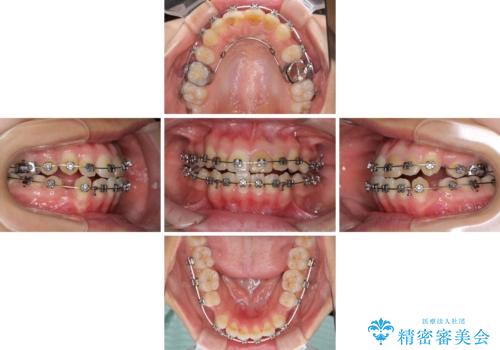

八重歯の抜歯矯正 費用を抑えた矯正装置

- 矯正装置

- メタルブラケット

- 治療期間

- 2年6ヶ月

- 上の八重歯を気にして来院された患者様です。

受け口傾向にあるため、上顎前歯の叢生解消とともに下顎前歯を後方へ移動させることを目的とし、上下左右の第一小臼歯4歯を抜歯することとしました。